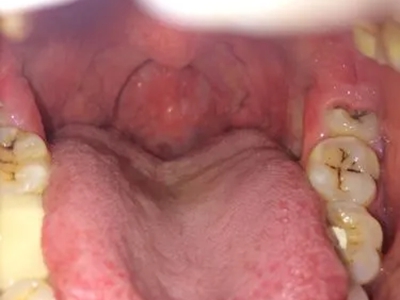

咽后壁

红肿

淋菌性咽炎咽后壁红肿图

淋菌性咽炎患者的咽后壁发生炎症反应,出现明显红肿,两侧扁桃体也发生肿大,张口能看到蚕豆大小的鲜红色扁桃体,表面没有明确的炎性分泌物,但是能够看到充血的血丝。